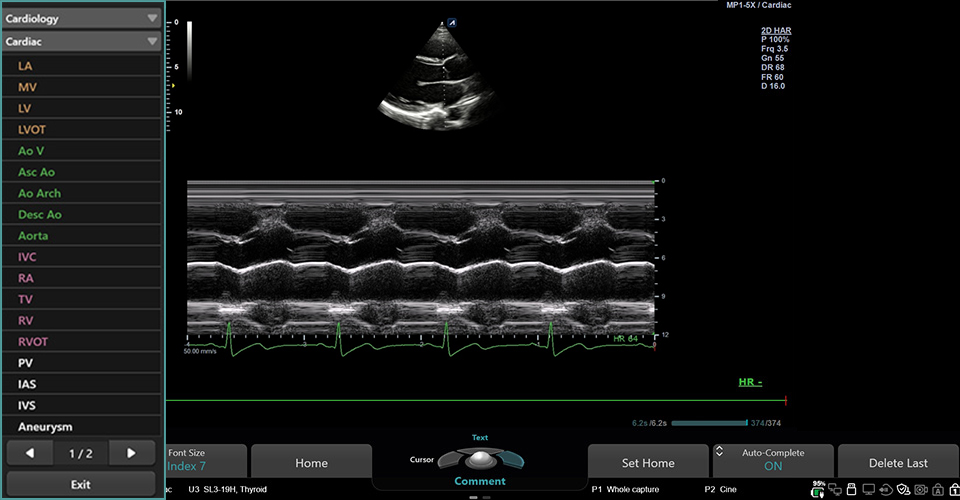

MP1-5X(NEW)

X+ Crystal Signature™ phased array (1~5MHz)

Application:

Cardiac, TCD, EM, Abdomen, Pediatric